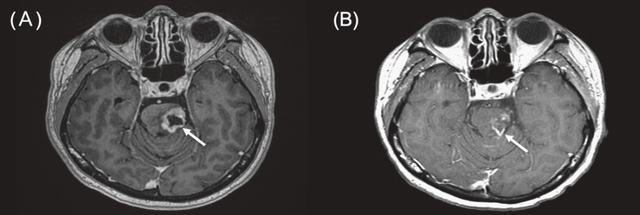

病例2

一名68岁女性,患有三阴性浸润性小叶及导管乳腺癌(左乳),出现小脑转移。她此前接受过全身化疗和立体定向放射治疗(SBRT),但出现颅内进展。BNCT治疗后MRI显示肿瘤显著消退,患者疼痛和肢体无力症状改善,未出现明显毒性反应。